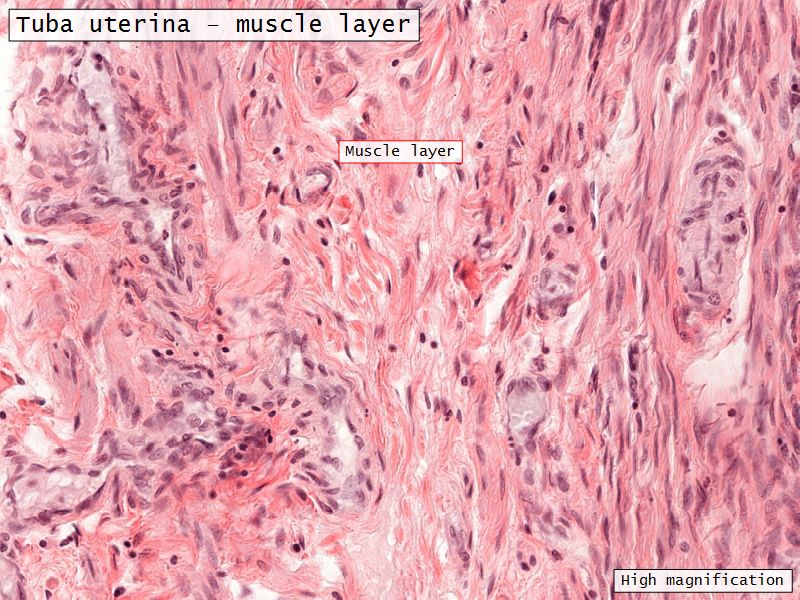

Muscular layer

- Ill-defined

- Inner circular

- Outer longitudinal

- Play role in moving zygote towards uterus